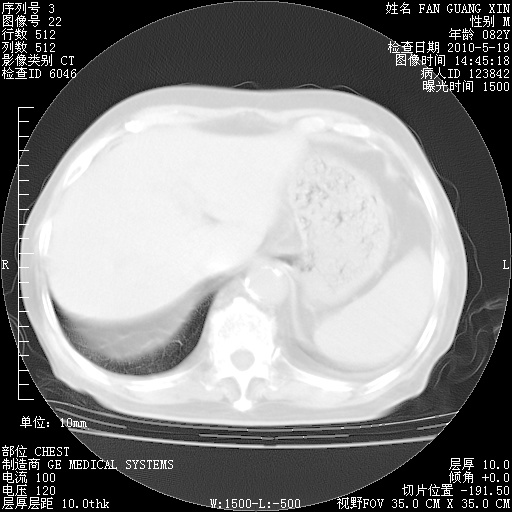

复查肺部CT,明显好转。为什么发热呢?

治疗3周后的肺部CT